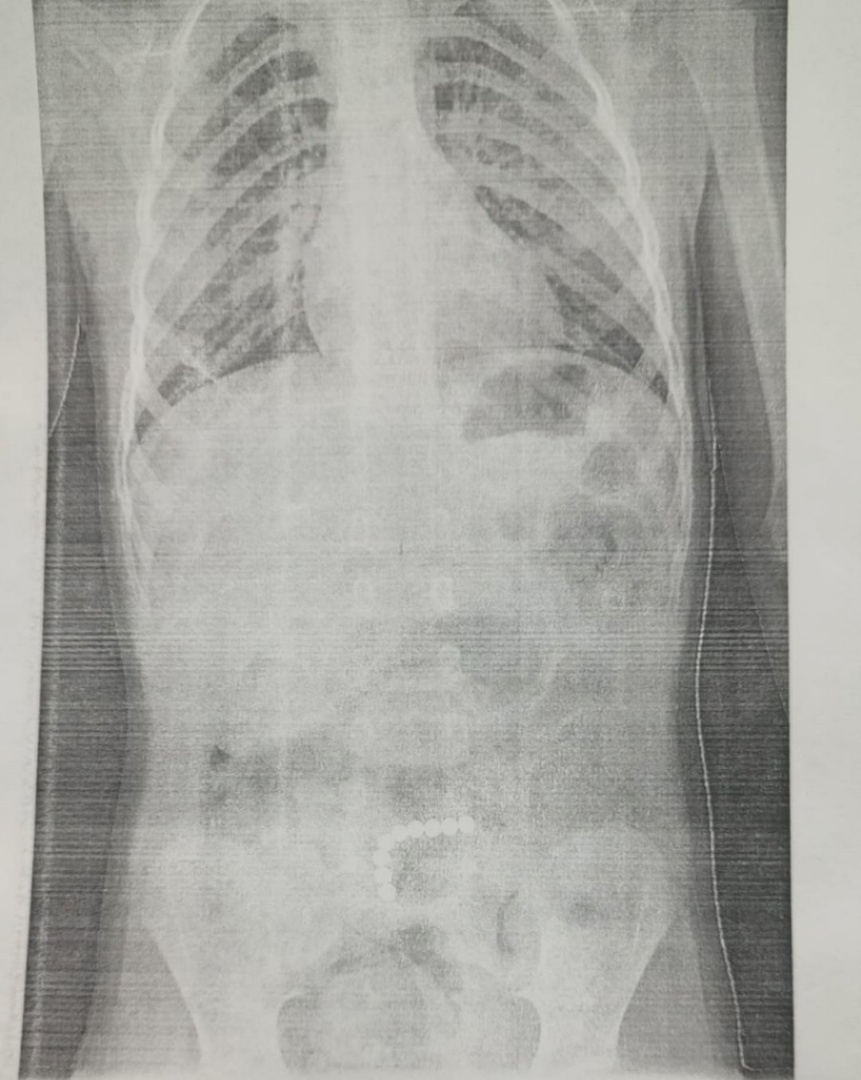

Спасли малыша. В Областной детской клинической больнице успешно прооперировали 4-х летнего ребенка. Мальчик проглотил 9 магнитыных шариков. Ребенок поступил в отделение детской хирургии ОДКБ с жалобами на боли в животе и многократную рвоту.

Предварительный диагноз - острый аппендицит. После узи и рентгена стало понятно, что в желудочно-кишечном тракте есть инородные тела и малышу требуется экстренная операция. Как говорят специалисты, в пищеварительном тракте магнитные шарики начинают притягиваться друг к другу и повреждать ткани. Если они находятся в соседних петлях кишечника, это приводит к перфорации его стенки.

На операции хирург Роман Черепанов и обнаружил сцепившиеся между собой магнитные шарики, которые уже спровоцировали разрывы тонкой кишки. Все 6 перфорационных отверстий врачи ушили, а магнитные шарики извлекли и удалили. Целостность и проходимость кишечника была восстановлена. Как оказалось, за несколько дней до госпитализации ребенок был в гостях, где во время игры с другими детьми мог проглотить магнитные шарики из детского конструктора.